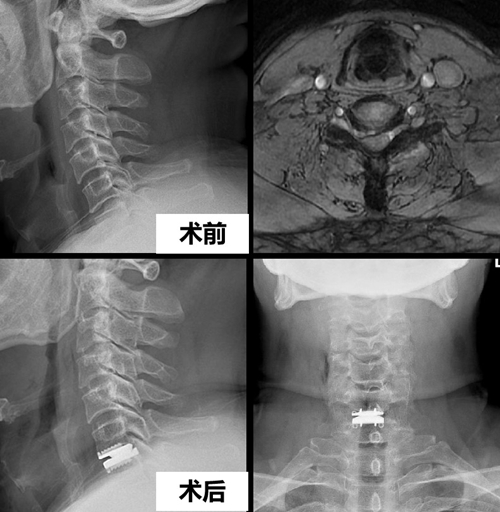

该例手术患者60岁,半年前出现肩颈部疼痛,同时伴有右手疼痛和麻木。先后尝试各种保守治疗方法,但症状未见明显缓解。1个月前,患者右上肢疼痛和麻木的症状明显加重,严重影响睡眠。为彻底解决这一问题,该患者慕名至我院刘浩教授门诊就诊。刘浩教授仔细阅片后发现其颈6/7椎间盘向右突出明显,像一块大石头一样严重压迫其右侧神经脊髓及神经根。刘浩教授结合病史、体检及影像学资料,确诊其为 “颈6/7椎间盘突出症伴不全脊髓神经损害”,建议患者入院进行手术治疗。从入院时的忐忑不安到出院时的平复如故,该患者住院时间仅为24个小时。

15时15分—16时45分:刘浩教授主刀行颈6/7人工颈椎间盘置换术;